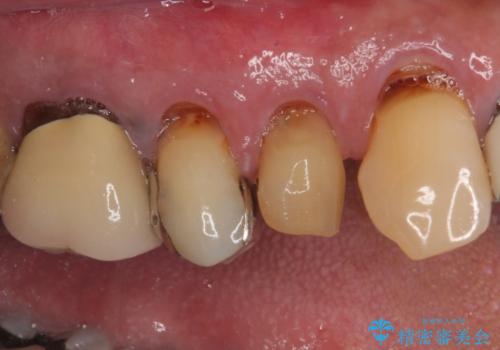

- 抜歯が必要なのでは?と近医で言われ、歯の保存を希望して来院された患者様です。

既に別の部位にインプラント治療を受けており、そのときの治療期間と苦労を鑑みて、何とか歯を残したいとのことで来院されました。

該当歯の状態としては何とか保存可能でしたが、予後不良のため、将来的にインプラント治療が必要となる可能性の高い状態でした。

当院での根管治療および歯周外科治療を併用した保存療法、並びに1DAYインプラントによる短期間インプラント治療の双方をご説明し、即日でインプラント治療を選択されました。

仮歯を用意した上で、抜歯即時埋入・即時荷重インプラントによる補綴治療を行うこととしました。